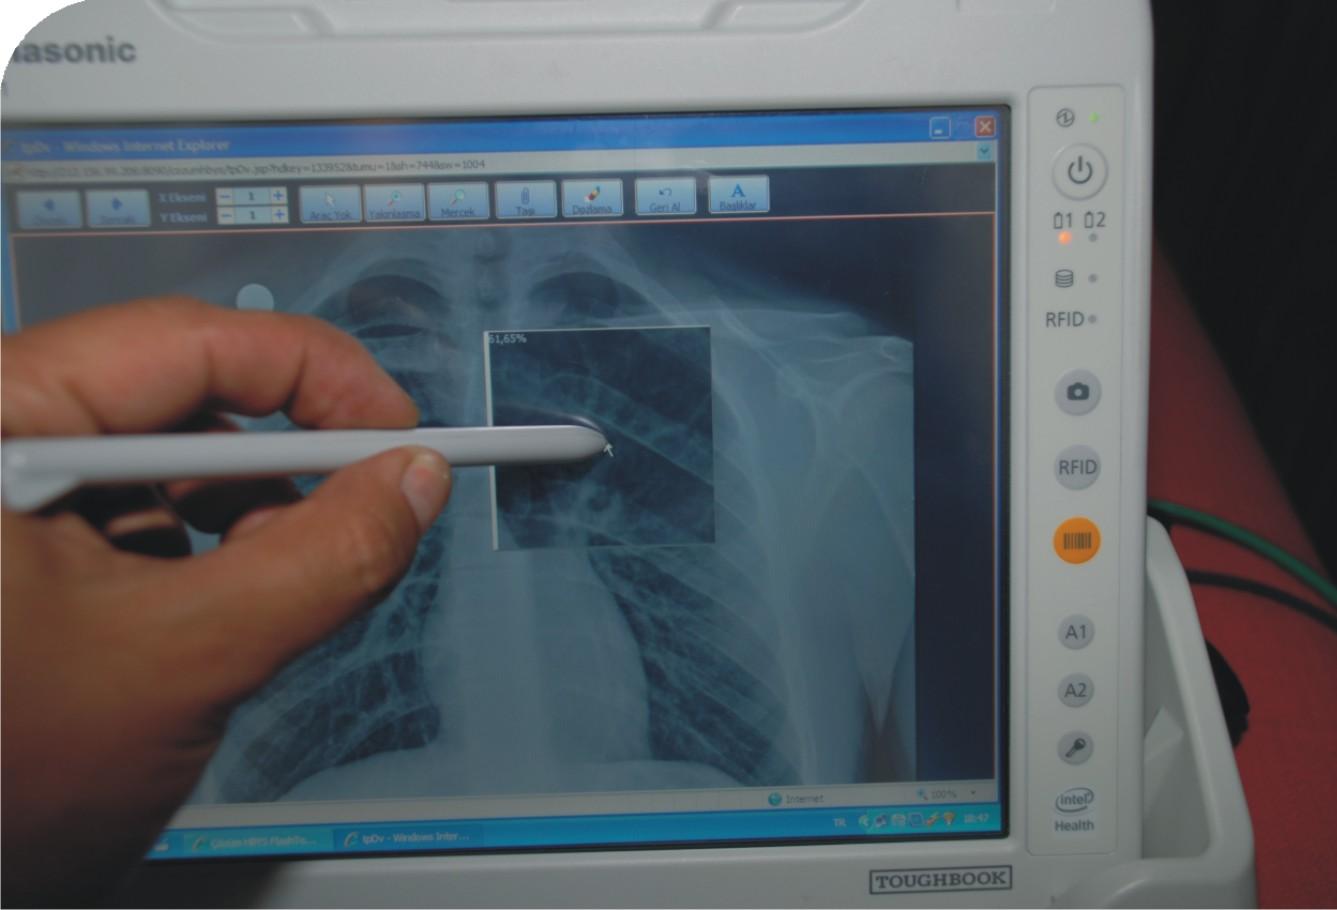

Endokrin Kliniği'nde hayata geçirilen Çözüm Medikal Klinik Asistan (MKA) uygulaması ile karar vericiler, hasta başından elektronik hasta kayıtlarına ulaşarak karar desteği buluyor, bulunduğu yerden veri ve istek girerek sağlıklı veri ve karar süreci yürütüyor.

Başhekim Yardımcısı ve Endokrin Klinik Şefi Doç. Dr. Tuncay Delibaşı uygulamanın özellikleri hakkında bilgi verdi.

Kliniğimizde Cisco'nun yürüttüğü kablosuz internet alt yapı çalışmaları tamamlandı. Yaptığımız araştırmalar sonucunda Panasonic'in hastane ortamları için yeni geliştirdiği Intel atom işlemcili CF-H1 ürününü ve üzerindeki Çözüm Medikal Asistan yazılımını tercih ettik.

Hastanelerde, zaman kavramının çok kritik olması nedeniyle hastanın işlemlerinin zaman kaybetmeden, hızlı ve doğru bir şekilde yapılması büyük önem taşıyor. Veri kaybının önlenmesi, her uygulamanın, her isteğin, her verinin kaydedilmesi ve anında ulaşılabilmesi gerekiyor. Hataya tolerans göstermeyen sağlık alanımızda daha kaliteli ürün ve hizmete ihtiyaç duyuyoruz. MKA, bize bu imkanı sağlıyor. Mobil veri girişi ile hasta teşhis, tedavi ve takip süreçlerimizi elektronik ortama taşıyarak, elektronik sağlık kayıtlarının (ESK) daha hızlı girilmesini ve hastanın başucundan gerçek zamanlı sorgulanmasını sağlıyoruz. Hastaya ait işlemlerin takip edilmesi ile birlikte klinik işlemlerimizi de güçlendiriyoruz.

MKA ile, hekimlerimiz ve hemşirelerimiz sağlık kuruluşları içerisinde kendi masalarına bağlı kalmaksızın HBYS'ye anında ulaşabiliyorlar. Bu proje kapsamında, yatan hastalara, özel hasta numarasını içeren RFID çipli ya da barkodlu bilek bandı takılıyor. Böylelikle hekimler ve hemşireler, RFID ve barkod okuyuculu MKA'ları kullanarak hasta hakkında gerekli bilgilere, günlük rutin kontrolleri sırasında, hastanın yanındayken dahi ulaşabiliyorlar.

MKA ile, hasta tedavilerinin kolayca planlanabilmesi, izlenebilmesi ve tüm sonuçların evraksız bir şekilde değerlendirebilmesini sağlıyoruz. Böylece, kağıt ve kalem kullanımını ciddi ölçüde azaltılıp, doğru teşhis ve tedavi oranını artırırken, tıbbi hata yapma olasılığını da en alt seviyeye indiriyoruz.